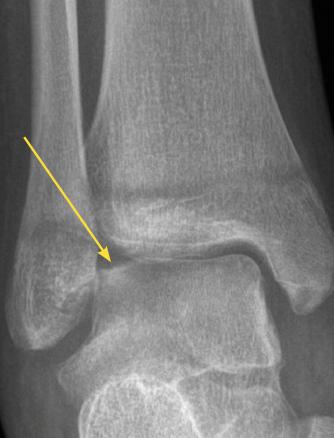

Lésion ostéochondrale du dôme talien avec un défect au coin supéro-externe.

Extrait de : Entorse de cheville de l’enfant